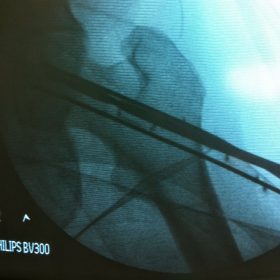

Διατροχαντήριο : Εξωαρθρικό κάταγμα, στην περιοχή ανάμεσα στο ελάσσονα και το μείζονα τροχαντήρα. Αντιμετωπίζεται χειρουργικά με ενδομυελική ήλωση τύπου γ-Nail. Δύο τομές 3 εκατοστών και 1 εκατοστού αντιστοίχως για την εισαγωγή και το κλείδωμα του ήλου μέσα στο οστό. Η μέθοδος είναι κλειστή,σχεδόν αναίμακτη,διάρκειας 30 λεπτών,με τη βοήθεια C-ARM (τηλεόρασης). Στον ασθενή παρέχεται οπτικό υλικό (όλα τα χειρουργικά στάδια) σε CD ή Στικάκι,λόγω της δυνατότητας καταγραφής του χειρουργείου από το C-ARM Ο ασθενής περπατάει άμεσα μετεγχειρητικά στις 5 ώρες μετά την επέμβαση και εξέρχεται από το νοσοκομείο σε 1 -2 ημέρες.

Υποτροχαντήριο :Εξωαρθρικό κάταγμα κάτω από τον ελάσσονα τροχαντήρα του μηριαίου οστού. Αντιμετωπίζεται χειρουργικά με ενδομυελική ήλωση τύπου Long γ-Nail. Δύο τομές 3 εκατοστών και 1 εκατοστού αντιστοίχως για την εισαγωγή και το κλείδωμα του ήλου μέσα στο οστό. Η μέθοδος είναι κλειστή,σχεδόν αναίμακτη,διάρκειας 60 λεπτών,με τη βοήθεια C-ARM (τηλεόρασης). Στον ασθενή παρέχεται οπτικό υλικό (όλα τα χειρουργικά στάδια) σε CD ή Στικάκι,λόγω της δυνατότητας καταγραφής του χειρουργείου από το C-ARM Ο ασθενής περπατάει άμεσα μετεγχειρητικά στις 5 ώρες μετά την επέμβαση και εξέρχεται από το νοσοκομείο σε 1 -2 ημέρες.